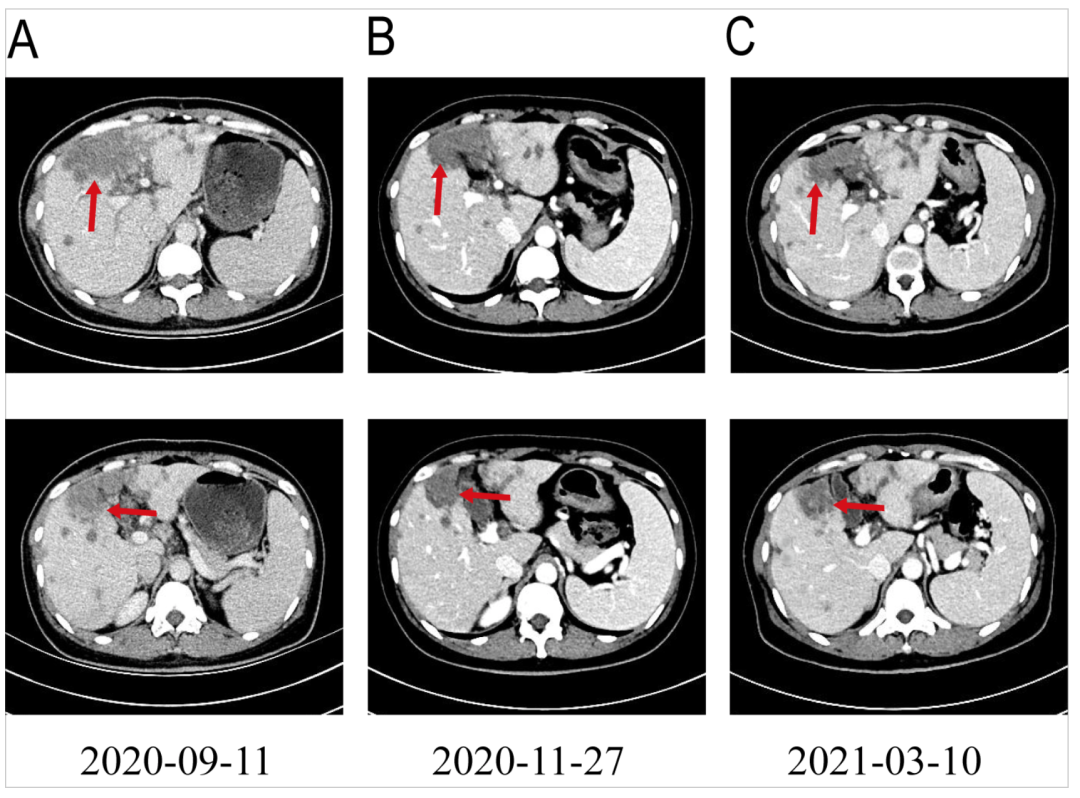

目前,已获FDA批准用于治疗FGFR2融合或重排的转移性胆管癌的药物有Futibatinib(TAS-120)和Pemigatinib等,但由于国内该类抑制剂的可及性差,价格昂贵,患者接受不了该药物治疗。经过充分沟通,我们为患者选择口服安罗替尼靶向治疗。患者自2020年9月15日开始接受安罗替尼(8mg,d1-14,q3w)治疗,口服安罗替尼4程、8程后复查CT提示肝内病灶较前持续缩小(Fig5),根据评价标准,患者疗效评价达部分缓解(PR)。安罗替尼治疗期间患者耐受情况良好,仅出现1级口腔黏膜炎、2级手足综合征及1级血清甘油三酯升高(按标准)。直到最近一次随访,患者一般情况良好,影像学复查提示肿瘤稳定。